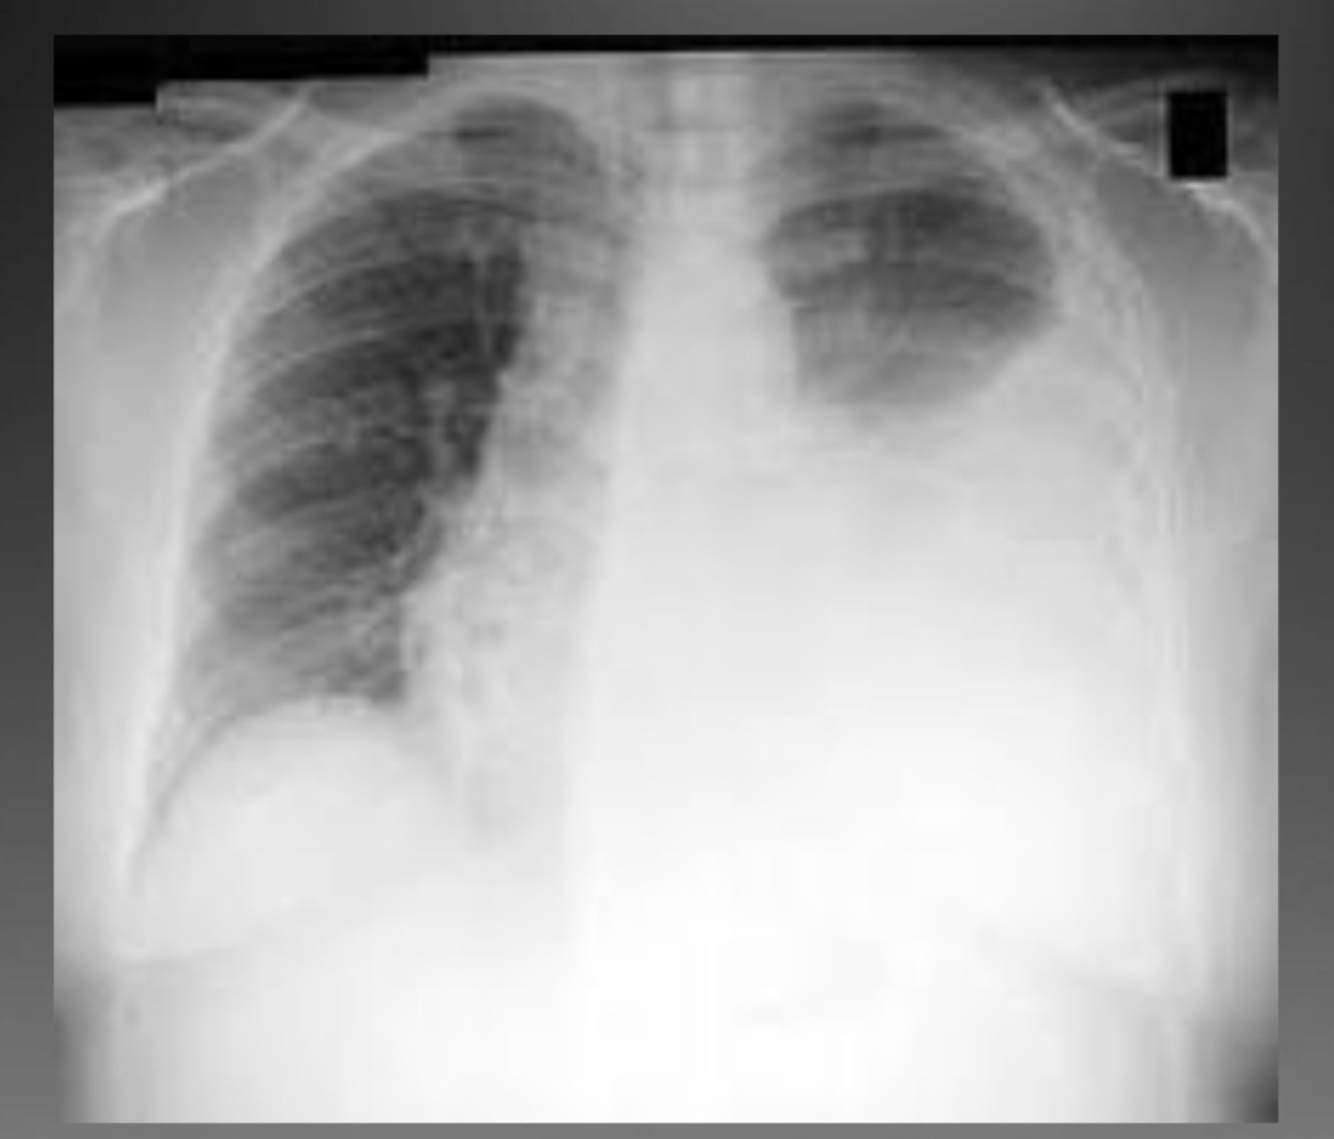

A

Pleural effusion (tb infected)